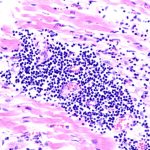

Исследователи сосредоточились на жителях побережья Атакамы, чтобы узнать, как часто те нападали друг на друга, какие увечья наносили и есть ли в этом какой-нибудь тренд. Для этого ученые описали останки 288 индивидов, обнаруженные в разных погребениях на берегу Чили. У всех на скелете остались следы серьезных повреждений — заживших при жизни или ставших причиной смерти, которые, скорее всего, нанесли им другие люди с помощью орудий. Они даже позволили узнать, в какую область тела (в том числе головы) чаще всего приходился удар и как это зависит от пола жертвы.